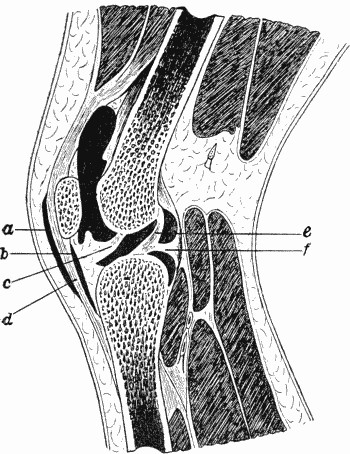

153 80.Section of Knee-joint showing Extent of Synovial Cavity

156 81.Extension applied by means of Ice-tong Callipers for Fracture of Femur